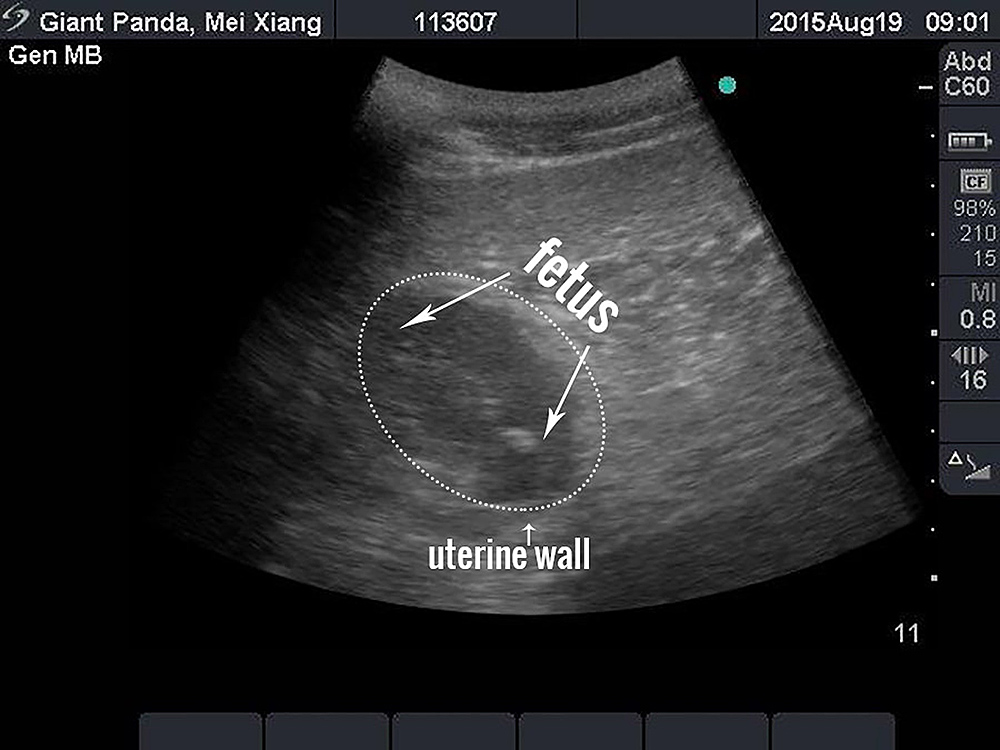

2015年8月19日,美国史密森尼国家动物园和保护生物学研究所首次公布大熊猫美香的超声检查图像。大熊猫美香是华盛顿国家动物园的明星,她于今年4月26日和27日接受了人工授精,其中新鲜精子来自华盛顿国家动物园的熊猫添添,冷冻精子来自居住在中国的大熊猫辉辉。据超声结果显示,美香可能在下周或者9月初生产。